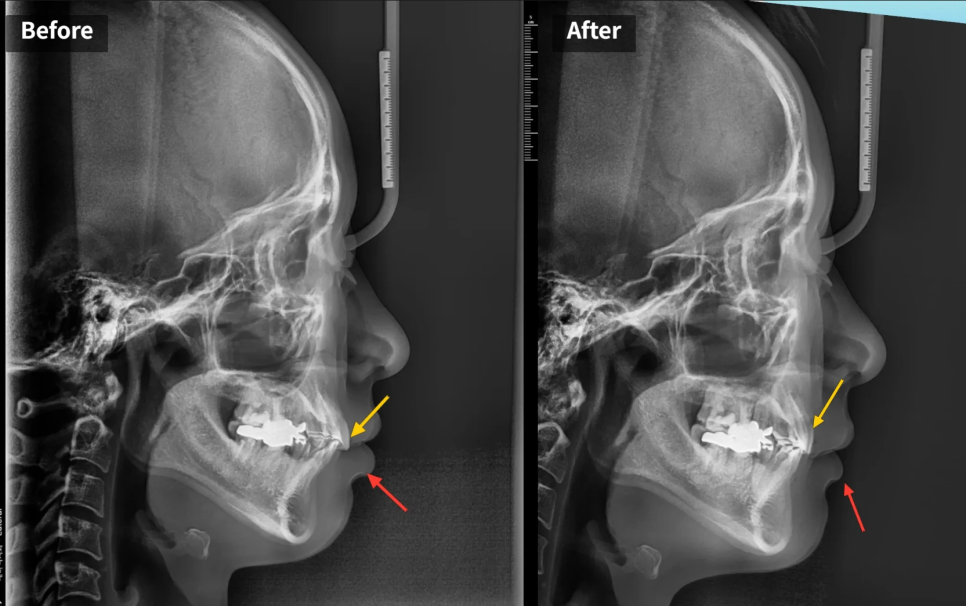

전후 엑스레이 비교

전후 측면 엑스레이를 비교해 보면 변화가 더욱 명확합니다. 이전에는 윗앞니가 아랫입술을 밀어내면서 입술이 볼록하게 나와 있었는데, 윗앞니가 충분히 후방이동하면서 그 원인 자체가 사라졌습니다. 결과적으로 위아래 입술의 균형이 맞아지고, 충분한 후방이동이 달성된 것을 확인할 수 있습니다.

전후사진 비교: 앞니(노랑)가 아랫입술(빨강)을 밀어내던 모습이 사라졌습니다

측면 두부 방사선 사진을 분석해 보니, 윗앞니가 아랫입술을 누르면서 입술이 말려나오는 양상이 확인되었습니다. 쉽게 말해, 윗앞니가 앞으로 나와 있어서 아랫입술을 밀어내고 있었던 것입니다. 이 말은 곧, 윗앞니를 뒤로 넣으면 아랫입술도 자연스럽게 뒤로 들어올 수 있다는 의미이기도 합니다.

윗니(노랑)가 아랫입술(빨강)을 밀어내고 모양새가 확인됩니다